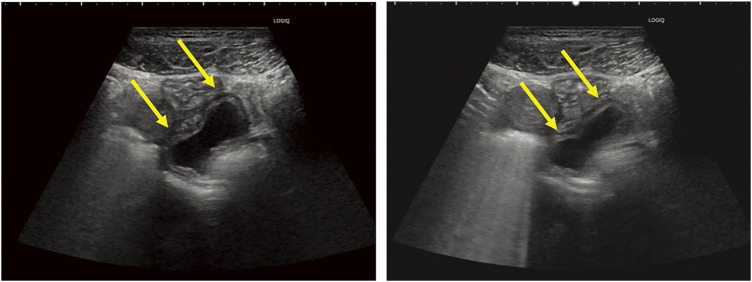

Case presentation: A woman in her thirties visited the emergency department with persistent lower abdominal pain. Physical examination and laboratory tests, including those for tumor markers, were unremarkable. CT revealed a cystic mass near the uterus, and pelvic MRI revealed a cystic lesion that had migrated during follow-up imaging. Cine MRI showed peristaltic movements within the lesion, and abdominal ultrasonography confirmed a cystic structure with wall movements resembling intestinal peristalsis. Based on these findings, the diagnosis of a noncommunicating small bowel duplication cyst was made.The patient underwent a laparoscopic single-port partial resection of the ileum. A cystic lesion located 75 cm proximal to the terminal ileum was excised along with a segment of the small intestine. Histopathological examination revealed a duplicated cyst lined with the small intestinal mucosa, confirming the diagnosis. The postoperative course was uneventful, and the patient was discharged 1 week postoperatively.

Conclusion: This case highlights the utility of cine MRI and ultrasonography in the preoperative diagnosis of small bowel duplication cysts. In particular, cine MRI provides dynamic visualization of peristaltic movements within the cyst, enabling a confident diagnosis. The migration of the cyst observed on serial MRI examinations further corroborated the origin of this duplication. These findings emphasize the importance of advanced imaging modalities in the diagnosis of rare intestinal anomalies. Preoperative diagnosis of small bowel duplication cysts can be significantly enhanced by using cine MRI and ultrasonography to detect peristaltic movements. These modalities offer critical insights that aid timely surgical intervention and improve outcomes.